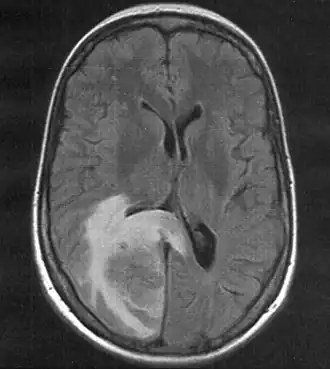

Métastase cérébrale

Une métastase cérébrale est une dissémination de cellules cancéreuses (métastases) dans le tissu cérébral. Cela désigne des tumeurs malignes originant de l'extérieur du cerveau.

Les métastases cérébrales viennent souvent du cancer du poumon, du cancer du sein, du cancer du rein et de mélanome malin[1]. Ce sont les tumeurs les plus fréquentes au niveau du cerveau[2]. Elles peuvent se faire sentir, entre autres, par des maux de tête, des troubles neurologiques, des convulsions et des changements d'attitude. Le traitement et les chances de guérison dépendent de nombreux facteurs, mais les métastases cérébrales ont généralement un pronostic défavorable.

- Les métastases les plus fréquentes sont les métastases multiples, qui se caractérisent par la présence de plusieurs métastases cérébrales.